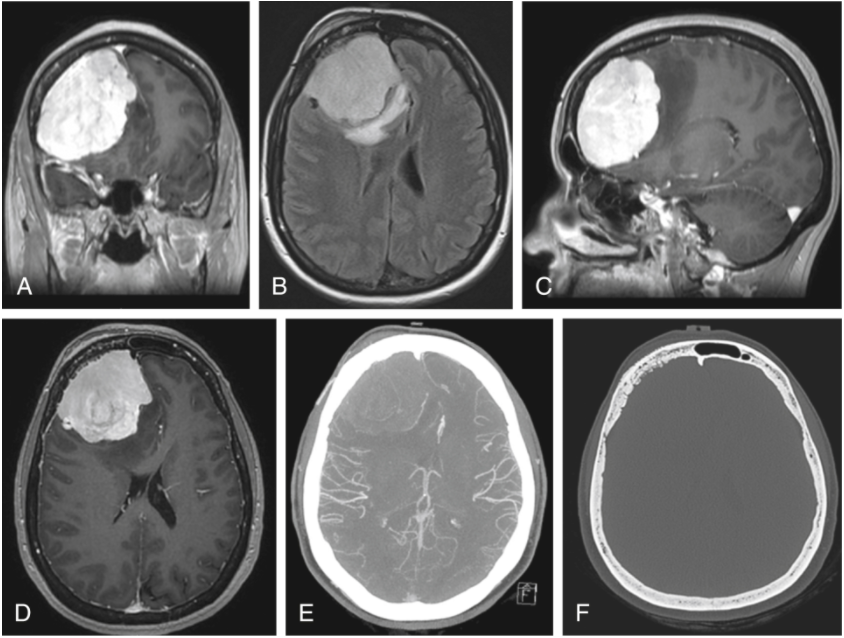

惡心、腹瀉、頭痛,1級(jí)腦膜瘤患者全切治療記錄

惡心、腹瀉、頭痛,1級(jí)腦膜瘤患者全切治療記錄,在一次外出旅行中,一名中年患者出現(xiàn)惡心、腹瀉、頭痛和定向障礙。到達(dá)當(dāng)?shù)蒯t(yī)院后,發(fā)現(xiàn)出現(xiàn)癲癇發(fā)作活動(dòng)的言語(yǔ)困難。CT和MRI掃...